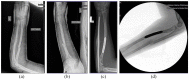

AP (a) and lateral (b) radiographs following initial closed reduction and casting of a 12-year-old female who suffered a left bone forearm fracture. (c) Radiograph of the forearm at the time of ulnar ESIN removal. (d) Lateral fluoroscopic radiograph demonstrating refracture of the ulnar shaft 12 weeks after ESIN removal.